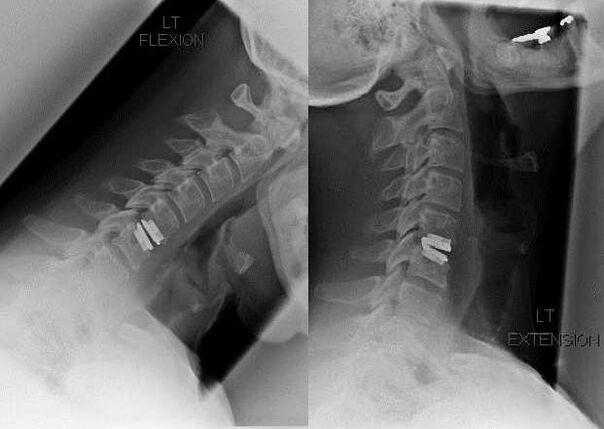

chirurgischer Eingriff

Zu den Indikationen für einen chirurgischen Eingriff zählen die Unwirksamkeit einer konservativen Behandlung sowie Komplikationen der zervikalen Osteochondrose, beispielsweise diskogene Myelopathie, Wirbelarteriensyndrom und radikuläres Syndrom. Um das Rückenmark, die Blutgefäße und die Wirbelsäulenwurzeln zu entlasten, werden folgende Operationen durchgeführt:

Bei der Operation können Knochen- und Bänderfragmente sowie Bandscheiben ganz oder teilweise entfernt werden. Bei kleinen Hernienvorsprüngen wird häufig eine Laserverdampfung des Bandscheibenkerns durchgeführt.

Nach der Entfernung von Wirbelstrukturen ist häufig eine Stabilisierung der Bewegungssegmente der Wirbelsäule durch Wirbelsäulenversteifung oder die Installation von Knochen- und Hautautotransplantaten erforderlich.